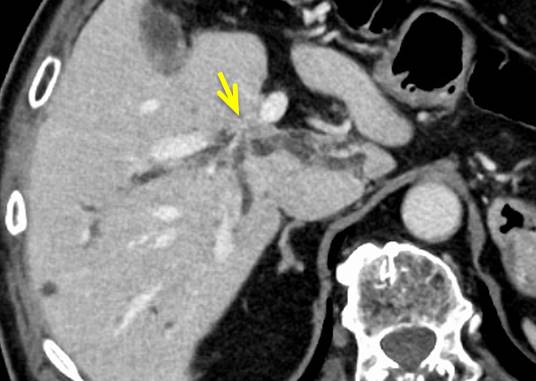

CT:

肝内胆管の拡張の起始部に壁肥厚(黄色矢印)

を認めますが、明らかな腫瘤は指摘できません。